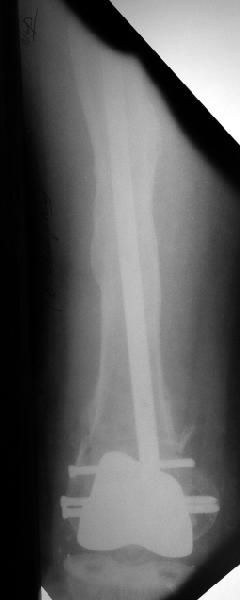

Глубокоуважаемые коллеги, Мужчина 41 года поступил с повторным (предыдущий в 2001 г.) переломом (3-недельной давности) над протезом коленного сустава.

В 1994 множественная травма, в том числе открытый перелом надколенника, осложнившийся гнойным артритом, и на этой же стороне перелом диафиза бедра (лечили в аппарате). В 1998 г. выполнено эндопротезирование коленного сустава.Предыдущий перелом (3 года назад) лечили консервативно, сросся при неустраненном смещении дистального блока бедра кзади ~ на 1 см.Амплитуда движений в коленном суставе перед последним переломом была ~90 градусов. Ходил без дополнительной опоры.Снимки в приложении. Какие будут предложения по поводу оперативного лечения в нынешней ситуации? У нас споры между ретро- и антеградным закрытым интрамедуллярным остеосинтезом.

A male 41 years old transferred to our unit with 3 week old femoral fracture near the knee prosthesis after a mimimal fall. In 1994 he sustained multiple injury with open patella fracture (complicated with septic arthritis), and ipsilateral femoral shaft fracture treated by ex-fix. TKA performed in 1998. In 2001 he got a periprosthetic fracture which was treated nonoperatively and healed with ~1 cm dorsal displacement of the distal femoral block. Knee ROM prior the recent injury was about 90-95 degrees. He didn't use walking aid.Images attached. I request your suggestions regarding surgical options in the situation? We mostly discuss ante- vs retrograde closed nailing.

В итоге сделали антеградный остеосинтез. В дистракторе свежий перелом вправился сразу, а вот старый - оставил проблему, дистальный отлмомк остался все равно кзади. И гвоздь бы прошел кпереди от него, а ретроградный - перфорировал бы передний кортекс. Так что пришлось еще сделать чрескожную остеотомию через перелом, чтобы малость мобилизовать дистальный отломок. Снимки в прилжении.

The radiographs look excellent and a good outcome would be anticipated. The idea to osteotomize the femur shaft to compensate for the prior shaft malunion was clever and should work fine.

I can't actually see the osteotomy on either radiograph. Is it more proximal than we see in these radiographs or so well aligned as to be not visible?